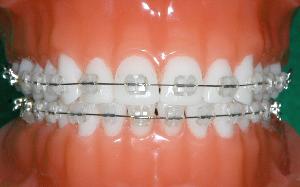

step4  矯正装置をつける

装置を装着し、動的治療が始まります。

『装置』とは、歯を動かすワイヤーと留める器具のことです。